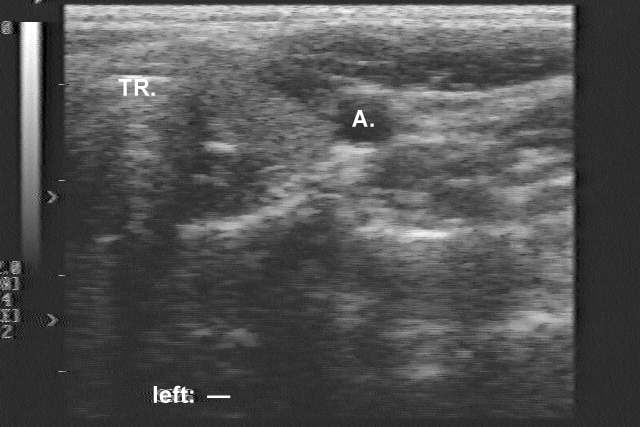

Ultrasonography: a moderately hypoechogenic nodule with cystic degeneration in the right thyroid.